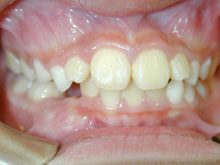

常滑市小林町在住 S.T様(15歳女性)

S.T様は下顎前歯の叢生が主訴でお母様と無料矯正相談で来院されました。

口を閉じる際に口元の緊張があり、横顔に突出感がありました。

以前に上顎前歯の部分矯正をされたご経験があるとお話しされておりました。

そのためか上顎犬歯の横幅(幅径)が通常より少なく思いました。

試料採取より診断の結果、上顎の前歯にも軽度の叢生があり、口元の緊張を改善し、

前歯の叢生の治療のために抜歯が必要であることを説明し、了承が得られたので本格矯正で治療をすすめることとなりました。

上顎前歯に軽度の叢生、下顎前歯に叢生がみられます前歯の上下の接触状態が緊密でなく軽度の舌癖の存在を疑います。

臼歯部は1歯 対 2歯で咬んでいます。

各ステージで順調に治療がすすみました。

![]() |

治療は順調に進みました。

犬歯の幅径が狭い事の対応として犬歯にダイレクトボンディングを行う、

下顎前歯のストリッピングを行うなどのプランを考えましたがその両方とも行うことなく動的治療を完了しました。

舌癖の存在は後戻りの大きな原因となりますので今後の保定治療でも注意が必要で、引き続き舌癖の改善を行います。

歯列矯正には副作用としてむし歯の発生、歯周病の悪化、歯肉退縮、歯根吸収、歯髄壊死などが起こる可能性があります。

治療期間:2年3ヶ月

治療費用:60万円